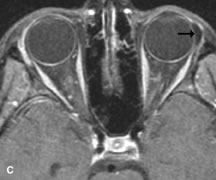

Application of a 90° RF pulse brings the excited nuclei into phase so that the net vector of their magnetic moments is directed perpendicular to the static magnetic field. Shortly thereafter, the magnetic moments of the nuclei spread out and point in different directions, leading to a loss of phase coherence and a resultant decay in signal intensity amplitude. The T2, or spin-spin relaxation time, is the rate of decrease in the signal of these excited nuclei as a result of the interaction and transfer of energy to unexcited adjacent nuclei. T2 ranges from a few milliseconds to a few hundred milliseconds and, for a given tissue, is always less than the Tl relaxation time. T2-weighted orbital images are easily recognized by a high-intensity signal from the vitreous (Fig. 9).5,8,16